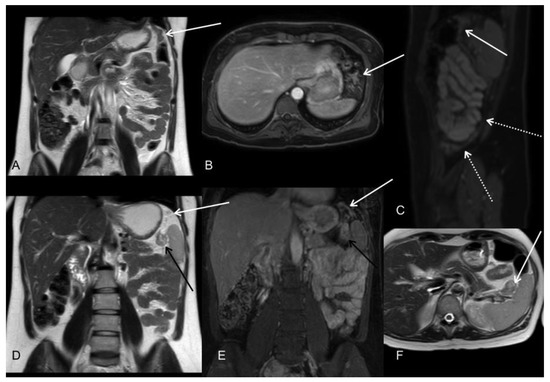

- Young, J.J.; Pahwa, A.; Patel, M.; Jude, C.M.; Nguyen, M.; Deshmukh, M.; Huang, L.; Mohammad, S.F. Ligaments and lymphatic pathways in gastric adenocarcinoma. Radiographics 2019, 39, 668–689. [Google Scholar] [CrossRef] [PubMed]

- González-Moreno, S.; González-Bayón, L.; Ortega-Pérez, G.; González-Hernando, C. Imaging of peritoneal carcinomatosis. Cancer J. 2009, 15, 184–189. [Google Scholar] [CrossRef]

- Sugarbaker, P.H.; Sardi, A.; Brown, G.; Dromain, C.; Rousset, P.; Jelinek, J.S. Concerning CT features used to select patients for treatment of peritoneal metastases, a pictoral essay. Int. J. Hyperth. 2017, 33, 497–504. [Google Scholar] [CrossRef] [PubMed]